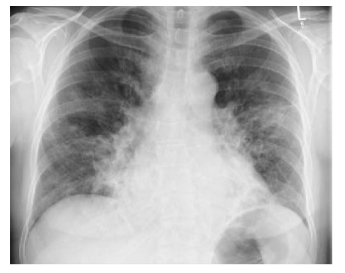

Uma paciente de 60 anos, sem comorbidades, iniciou há dois dias quadro de tosse com expectoração purulenta, febre e dispneia. O diagnóstico foi confirmado com a realização de radiografia de tórax representada na imagem abaixo.

O agente causador mais provável para a doença apresentada é: